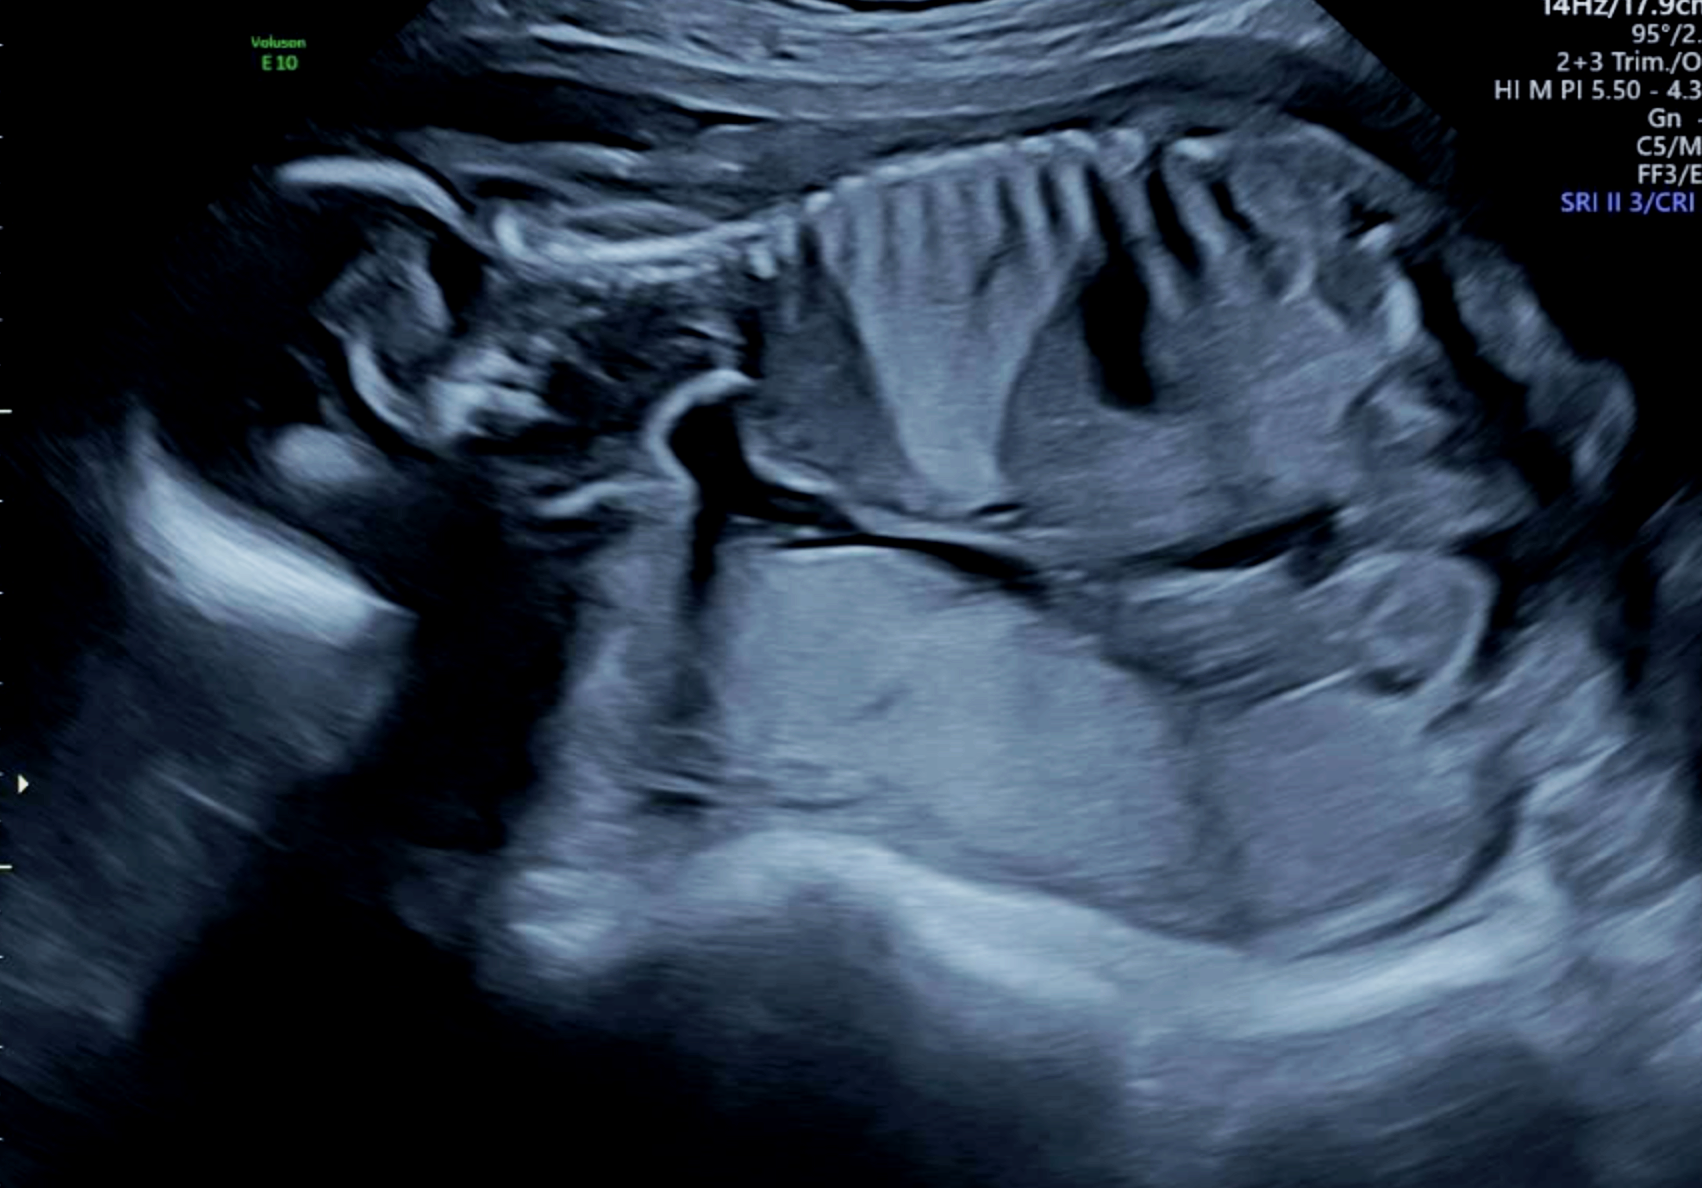

The bright wedge shape on this ultrasound is a lung malformation. This baby was diagnosed with a bronchopulmonary sequestration (BPS).